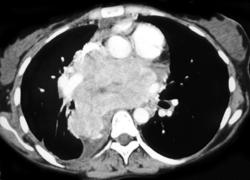

Left Breast Cancer With Internal Mammary and Axillary Nodes